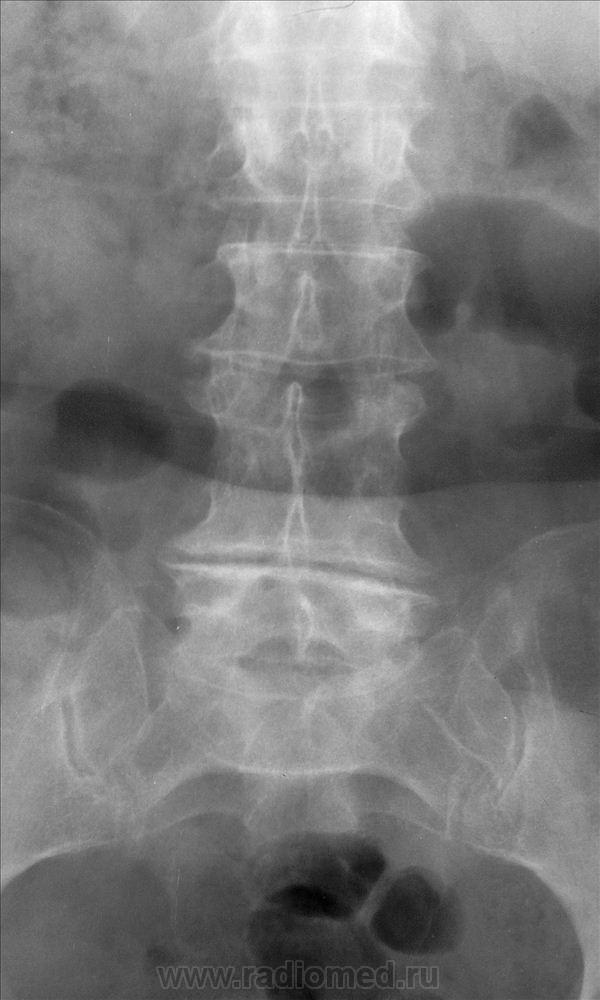

Добрый вечер, Александр Викторович.Интересно, это впервые выявленная находка или есть архив, анамнез?Жаль, остистые отростки не очень хорошо визуализируются-может быть, они тоже сращены.Может и нет.При врожденной конкресценции остистые отростки сращены.Здесь же локальный кифоз на уровне 3-4 позвонков, клиновидность тел, выраженное снижение высоты межпозвонковых дисков выше- и нижележащих.Больше данных за посттуберкулезнвй спондилит, вернее его последствия, хотя не факт, травма тоже могла так обезобразить позвоночник.Если можно, уточните анамнез, пожалуйста.

Вот и снимки

Диф. диагностика с посттравматическим и посттуберкулезным костным блоком. Дуги не сращены, насколько я смогла рассмотреть.

Конкресценция (врожденная). Отсутствие намека на реактивный остеосклероз, однородность костной структуры, указывают против инфекционного процесса.

Для врожденного смущает структура в задних отделах.

+ укорочение и деформация ножек дужек.

99,999% - за конкресценцию тел L4 и L5

(+ остеохондроз 2 ст. с антелистезом L3 1ст., остеохондроз 3ст. в L5-L6...) и